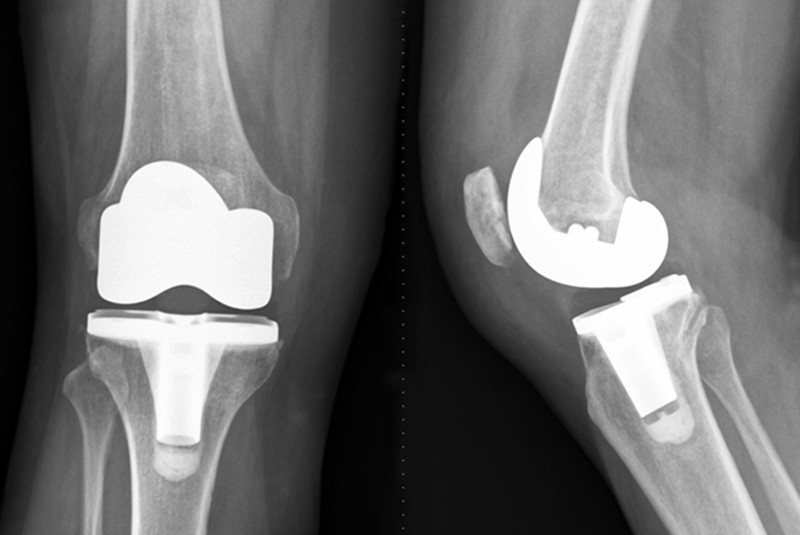

人工膝关节由金属和聚乙烯构成,置换手术也并非切掉整块骨头,而是用人工假体置换关节的表面,有些像戴个牙套,也可以根据病情,进行全膝关节置换和部分膝关节置换。这种手术的目的在于缓解疼痛,提高生活质量,改善膝关节功能。原则上适合所有年龄段的人,但由于人工关节有使用寿命,中老年患者进行置换得较多。医生也可能建议一些年轻患者推迟手术。

膝关节置换程序

进入麻醉后,开始手术,手术时间在1到2.5个小时,和医生的熟练程度关系很大,手术后患者可能会接受数小时的监控,直到麻醉效果消失。此后患者会在医院住几个晚上,有些患者可以在第三天出院。